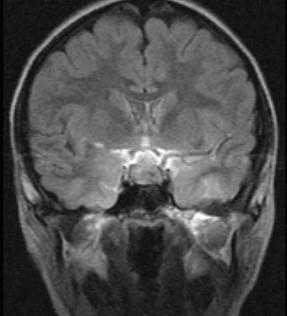

鞍区肿瘤(如图所示)的临床表现包括()A.内分泌功能障碍B.偏瘫C.失语D.视力、视野障碍E.原发性视乳头萎缩

问题 鞍区肿瘤(如图所示)的临床表现包括()

选项 A.内分泌功能障碍 B.偏瘫 C.失语 D.视力、视野障碍 E.原发性视乳头萎缩

答案 ADE